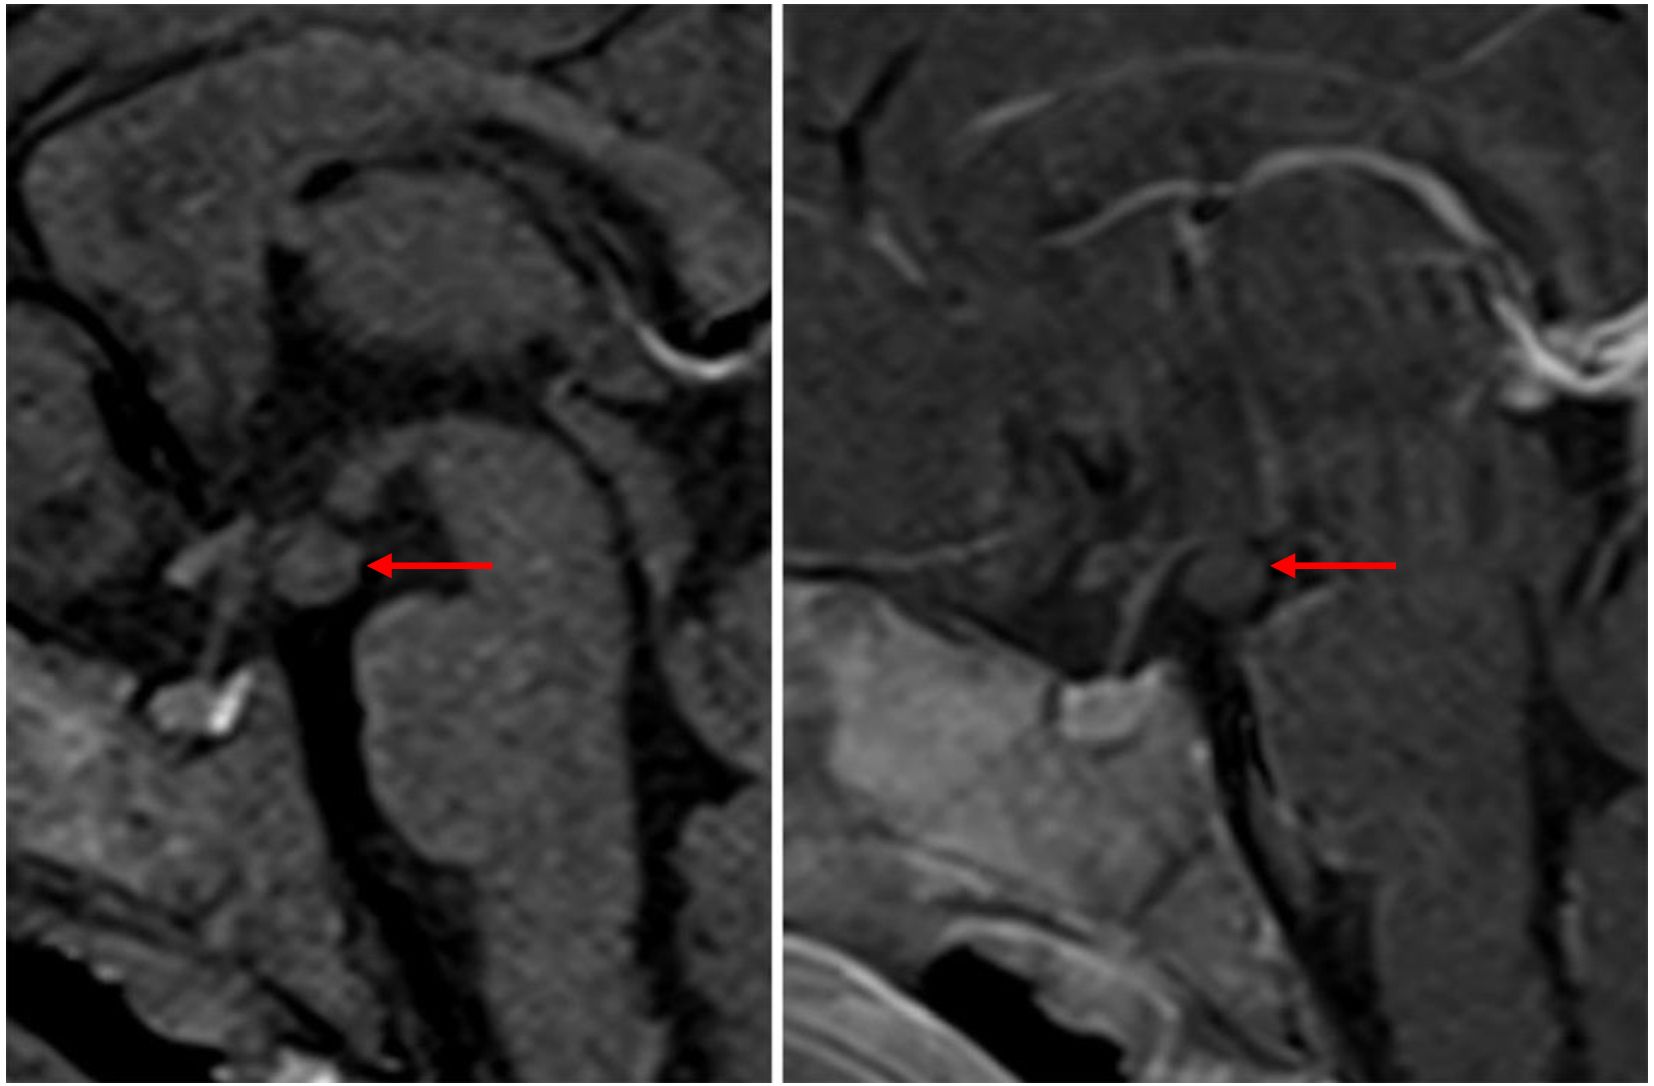

A 5.5-month female infant was referred for further evaluation due to prolonged vaginal bleeding. She is the third child of healthy, unrelated parents, born from an uneventful pregnancy at 38 + 2 weeks of gestation (birth weight 3,380 g, + 0.37 SDS; length 51 cm, +0.17 SDS). Her previous medical history was unremarkable, and developmental milestones were age appropriate. There were no data on previous infection, trauma, topical use of estrogen-containing cosmetic products, or sexual precocity in family members. Bloody vaginal discharge resolved spontaneously after 5 days. On physical examination, her height and weight were 1.19 SDS and 0.31 SDS, respectively. The breast development was Tanner stage II, with enlarged, normally pigmented nipples and no pubic or axillary hair. There were no caffe-au-lait spots, but large light beige discoloration with irregular margins, covering the left abdominal area, up to the left rib cage, was noted. Endocrine laboratory evaluation showed elevated basal gonadotropins with markedly elevated estradiol levels, measured during, and following the resolution of vaginal bleeding (Table 1). Serum tumor markers (α-fetoprotein, β-subunit human chorionic gonadotropin, carcinoembryonic antigen, cancer antigen 125, carbohydrate antigen 19–9) and thyroid function tests (free thyroxine, thyroid-stimulating hormone) were normal. Pelvic ultrasound revealed a slightly enlarged uterus measuring 1.96 × 1.45 × 3.09 cm with an endometrial thickness of 3.1 mm. No follicles, cysts, or tumors were detected in the ovaries (right ovary 1.58 × 0.82 cm; left ovary 1.54 × 1.14 cm). Because of extremely high estradiol levels, autonomous ovarian secretion was also considered, so both brain and pelvic MRIs were performed on the 24th day after bleeding. Estradiol levels, measured simultaneously in two different laboratories, were about four times higher than initial (Table 1). Pelvic MRI revealed a cyst in the right ovary measuring 17 mm, and repeated pelvic ultrasound also described an avascular right ovarian cyst 20 × 14 mm. However, a brain MRI confirmed the diagnosis of HH (isointense peduncular lesion originating from mammillary bodies, 6 mm in diameter) (Figure 1).

Figure 1. T1-weighted sagittal MR images in a 5.5-month-old infant with central precocious puberty and exaggerated estradiol secretion before and after gadolinium administration demonstrated a hypothalamic hamartoma. A rounded mass is located below the floor of the third ventricle, projecting into the suprasellar cistern behind the infundibulum of the pituitary gland. It is isointense to grey matter on T1 weighted images and does not enhance after gadolinium administration.